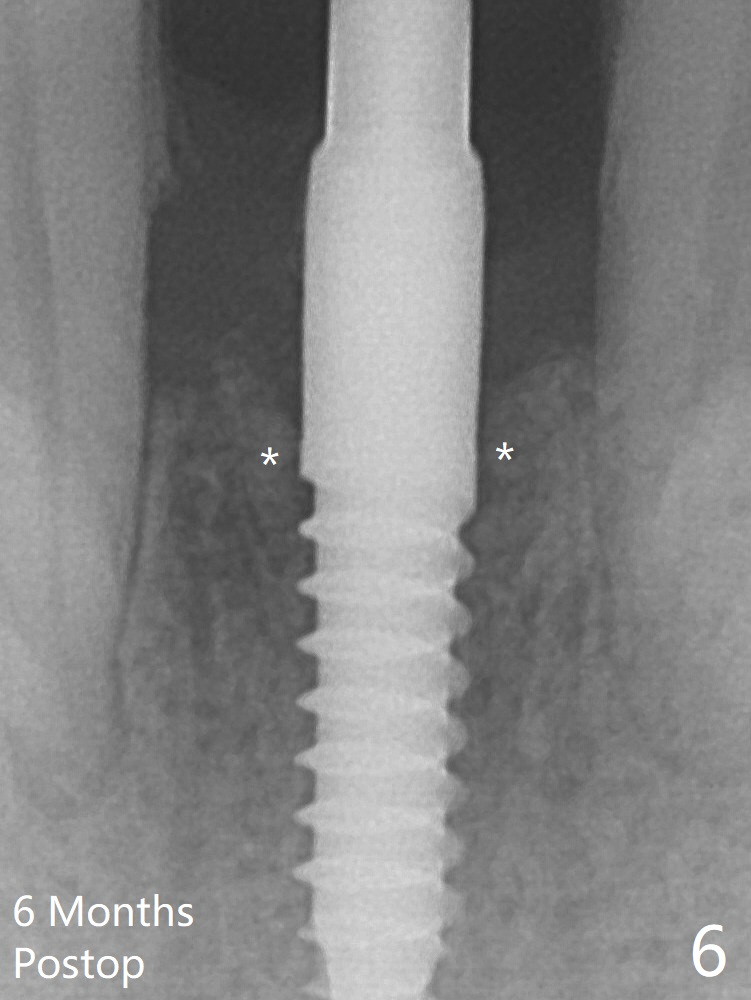

Since the gingiva is as thick as 7.5 mm (Fig.3 arrow), a 3x14 mm 1-piece implant with 4 mm cuff is placed (Fig.5); three implant threads are outside the native bone; with allograft (*) placed and the neighboring crests being coronal to the threads, the chance of periimplantitis should be remote. An immediate provisional is fabricated to contain the graft in place. The top 3 threads appear to be contacted by the newly formed crestal bone 6 months postop (Fig.6 *). Bone appears to have grown into the space between implant threads 6 months post cementation (13 months postop).